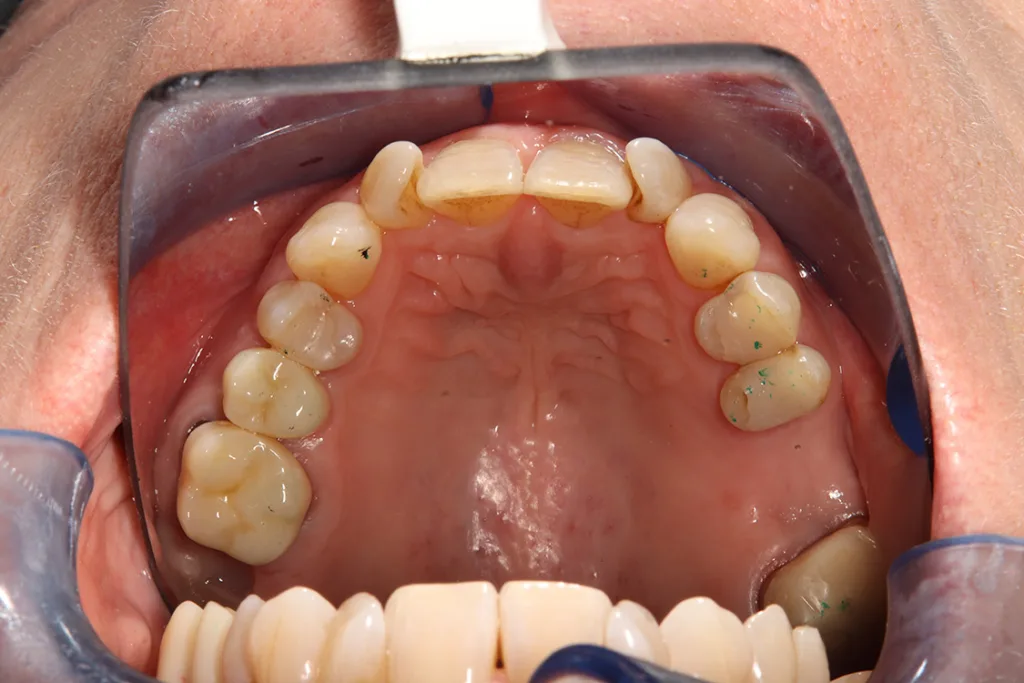

Die additive Fertigung von festsitzendem Zahnersatz kann in zwei weitere Gruppen eingeteilt werden: der provisorische Zahnersatz sowie der definitive Zahnersatz (Abb. 4a und b). Die Anforderungen für permanente Restaurationen sind deutlich höher, was erklärt, weshalb nicht jedes Komposit bzw. Material für definitive festsitzende Restaurationen zugelassen ist.

Die Hauptindikation der additiv gefertigten Restaurationen sind Einzelzahnrestaurationen wie Inlays, Onlays, Veneers, Teilkronen oder Vollkronen (Abb. 5). Aber auch der Einsatz als kurzspannige Brücke (provisorisch oder definitiv) ist möglich (Abb. 6). Der Einsatz additiv hergestellter Non-Prep-Langzeitprovisorien stellt eine außerordentliche Indikation dar und wird von den Herstellern nicht aufgeführt (Abb. 7).

Non-Prep-Langzeitprovisorien können vor allem bei komplexer Gesamtrehabilitation sinnvoll sein. Diese Provisorien werden volladhäsiv eingesetzt und verbleiben als Aufbaufüllung vor definitiver Versorgung (Abb. 8a und b).